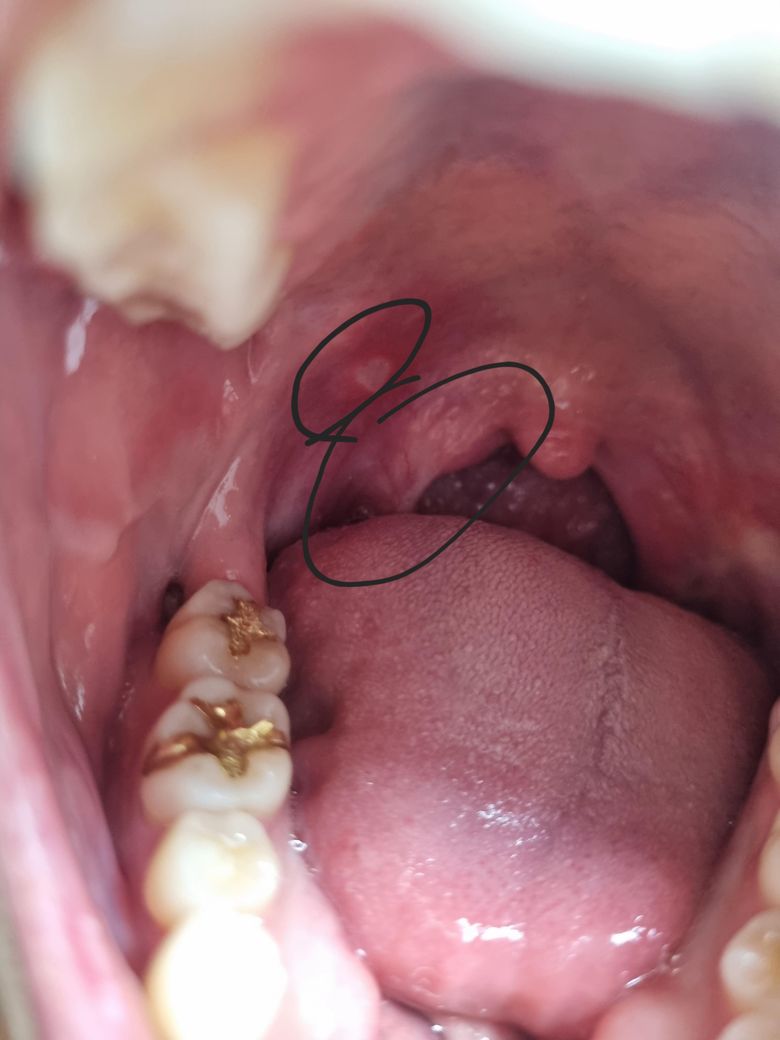

목젖 부근 아픔 및 입천장 구내염좀 봐주세료

한3일전부터 동그라미 친부분이 조금 불편해서 사진으로 찍어보니 구내염이있는것같고 목젖쪽은 잘모르겠는데 불편하고 살짝 아픕니다. 심각한건가요? 아니면 영양제잘챙겨먹으면 호전될까요?

올려주신 사진이 또렷하지 않아 목젖 주변은 잘 확인되진 않으나 바깥쪽 표시 부위에서 구내염 소견이 관찰됩니다.

충분한 휴식과 영양 섭취만으로도 회복이 가능하나 통증이 심한 경우 구내염 연고를 바르고 회복을 지연 시킬 수 있는 음주, 흡연, 자극적 음식의 섭취를 피하기 바랍니다.